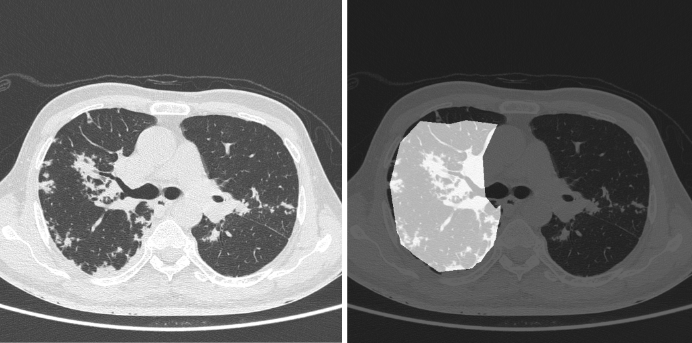

We tested our model using varied sets of data from different sources. We initially evaluated the model on our test set, consisting of 1330 images, in which COVID-19-positive samples had a prevalence of 20%. Our model gave a sensitivity of 0.963 (95% CI: 0.94-0.98) and a specificity of 0.936 (95% CI: 0.92-0.95). The dice coefficient on positive samples was 0.561. figures 2 and 3 show the superimposed masks on one of the slices.

Refer to caption

Figure 3: (Left) original image and (right) corresponding predicted mask.